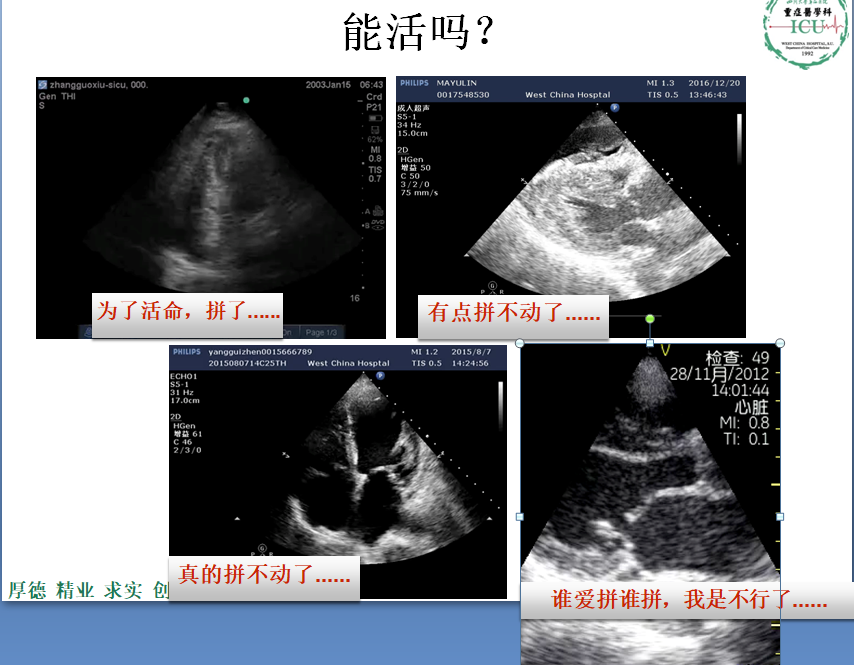

重症医学科是一个收治重症患者的科室,是与死神抢夺患者生命的战场。

重症医学科是一个收治重症患者的科室,是与死神抢夺患者生命的战场。通过向同学们介绍重症医学的内涵,用最真实、鲜活的例子为同学们树立先进榜样。该课程围绕国家对医学人才的需求出发,结合重症医学的发展,将医学专业教育与思政教育紧密结合在一起。结合学校发展定位和人才培养目标,构建全面覆盖、类型丰富、层次递进、相互支撑的课程思政体系。通过该课程使学生不仅仅掌握重症发病的病理机制,还要帮助其塑造正确的世界观、人生观、价值观,着力培养学生医者仁心的高尚品格,教育引导学生始终把人民群众生命安全和身体健康放在首位。为祖国的未来培养出一批政治坚定、技能扎实、勇于创新的新型复合型医学人才。